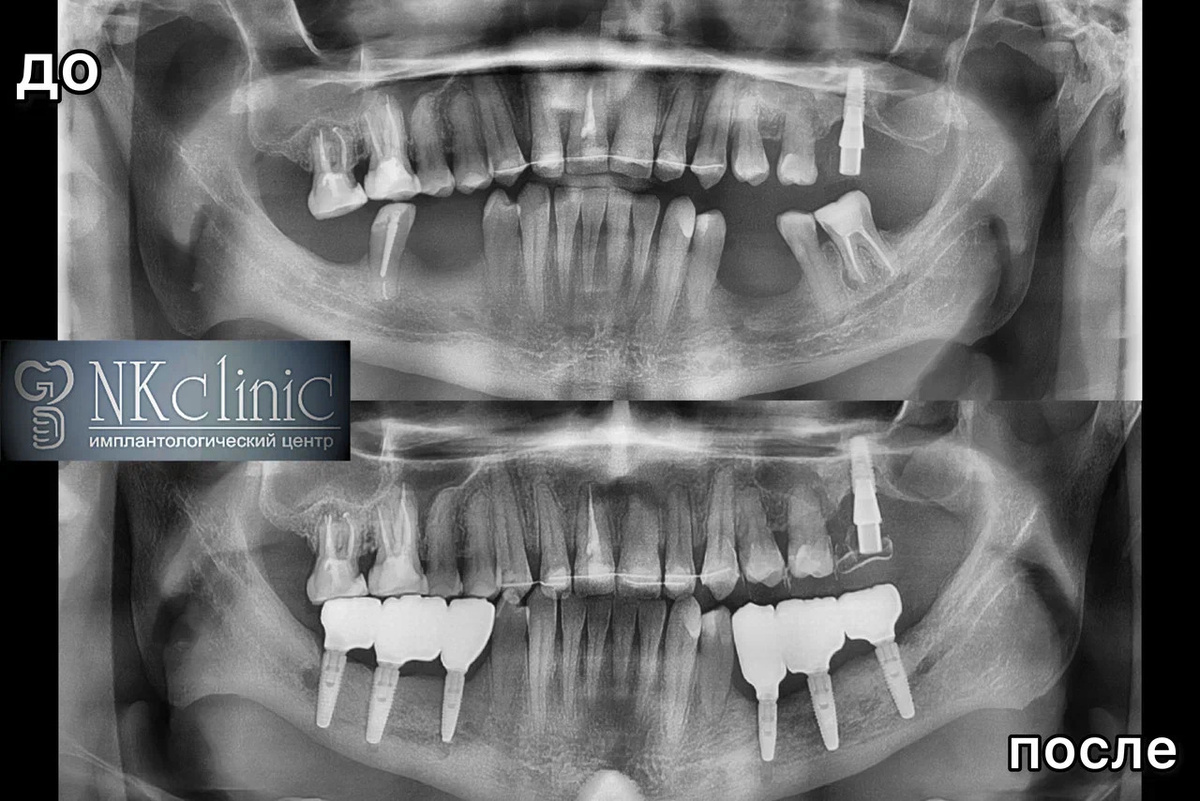

История пациента, который за пять лет перенёс 12 неудачных операции по наращиванию костной ткани и установке имплантов.

Данный пациент утратил жевательные зубы и обратился к врачам в родном городе. Ему пересадили костный блок и установили импланты, но они не прижились. Спустя четыре месяца — ещё два импланта, и снова отторжение. Врачи попытались повторно нарастить костную ткань на нижней челюсти, но это не привело к результату.

Всего пациент перенёс 12 неудачных операций и пять лет жизни, но вернулся к тому, с чего начал — атрофия костной ткани, отсутствие жевательных зубов. Ему хотелось опустить руки, проблема казалась слишком сложной.

На осмотре челюстно-лицевой хирург Давид Назарян поставил диагноз, стоматолог-ортопед Григорий Кялов назначил план лечения. Уже через неделю доктор Назарян провёл латерализацию нерва, удалил три несостоятельных зуба, нарастил костную ткань, установил шесть имплантов на нижней челюсти. Доктор Кялов установил временные коронки.

Через 20 дней после операции сняли швы, через три месяца провели лоскутную операцию. Спустя полгода после имплантации Григорий Георгиевич установил постоянные коронки. Лечение завершилось успешно.